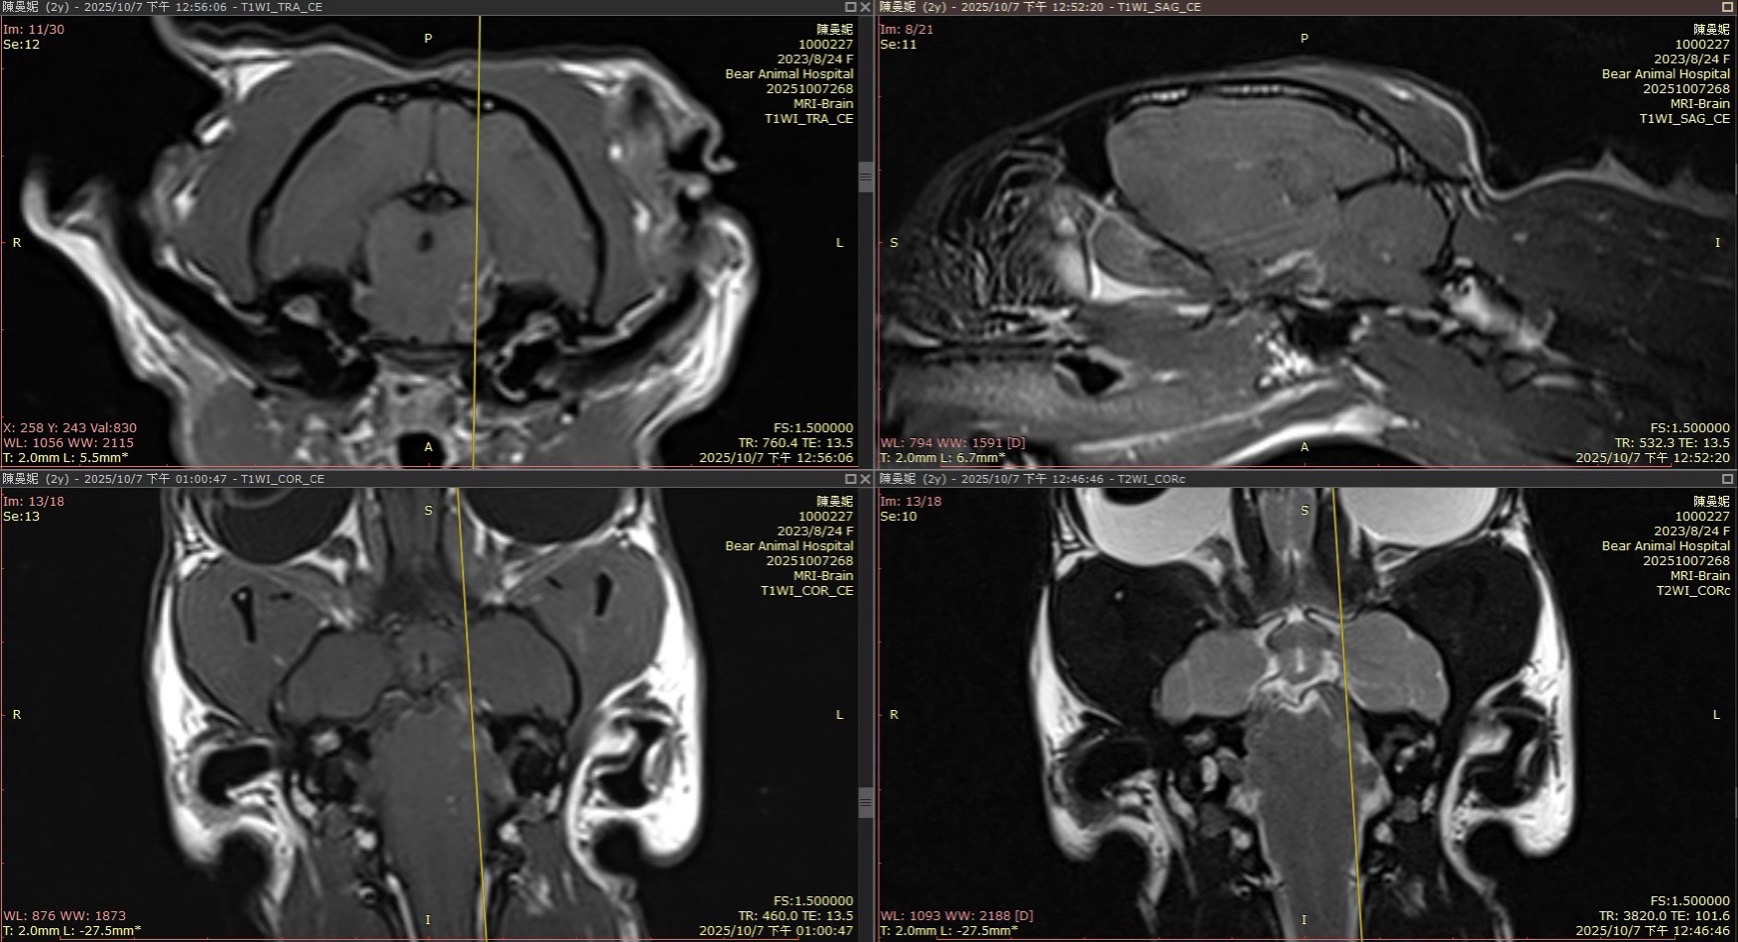

前陣子一隻2歲貓貓因瞳孔大小不一、四肢無力及精神食慾下降來院就診,核磁共振影像發現左側第三對及第五對腦神經腫大且顯影增強,最終診斷為大球淋巴瘤伴隨中樞神經侵犯 (Large cell lymphoma with CNS involvement)。

圖二、MRI顯示左側第三對及第五對腦神經腫大且顯影增強